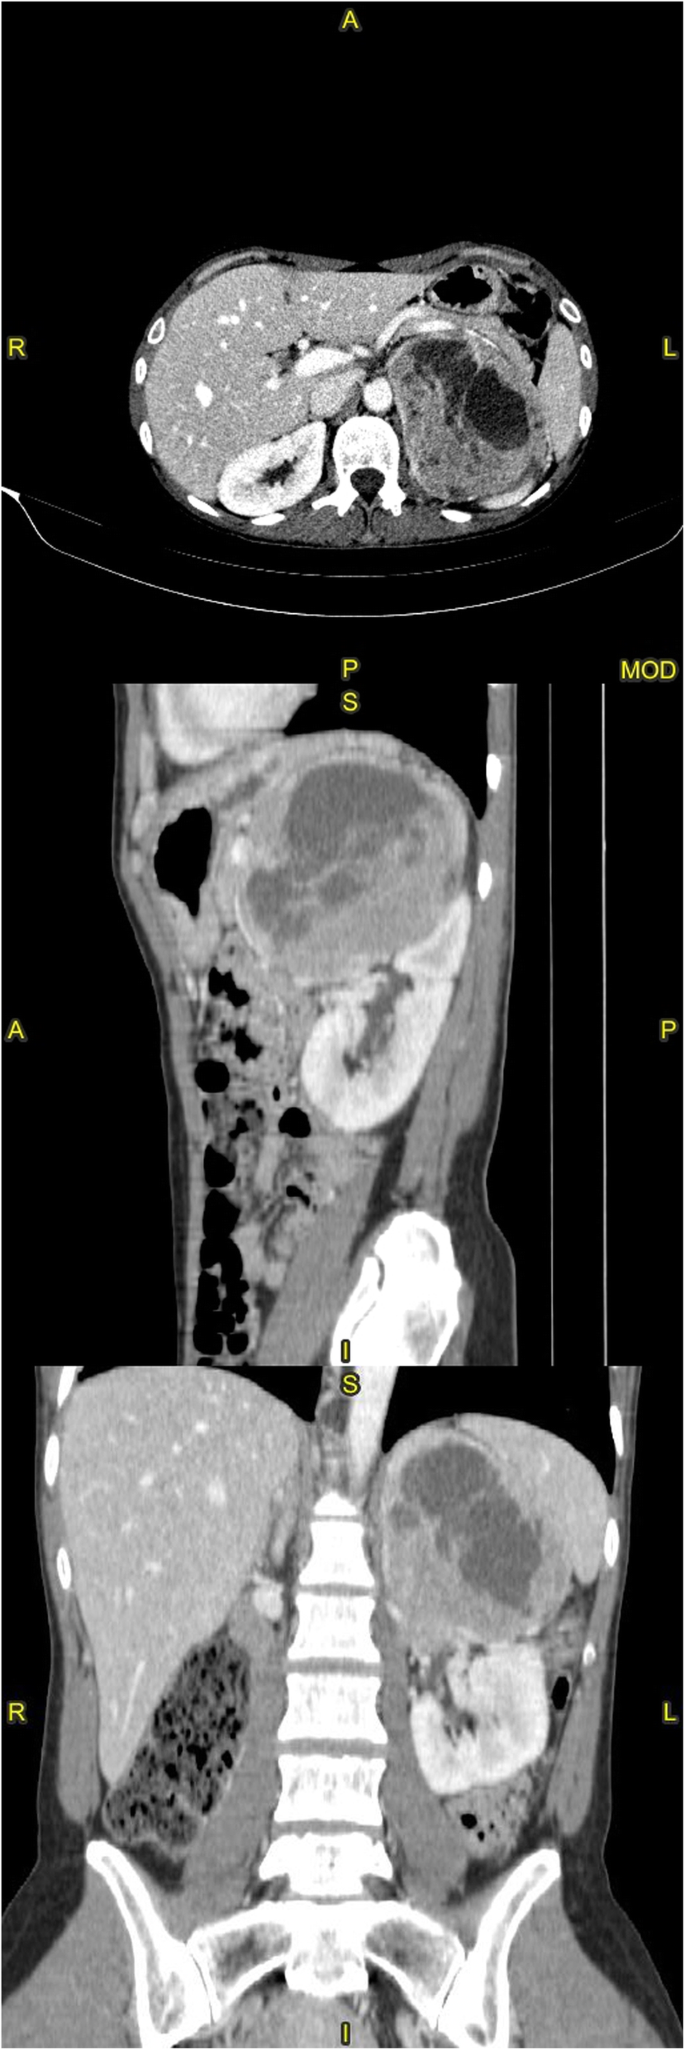

Because of the patient’s unremarkable medical history and abruptness of the crisis, a total body CT scan was requested in search of a diagnosis. The brain scan was negative; lungs were remarkable for diffuse ground glass infiltrates; finally, a 11.4-cm adrenal mass occupying the superior cap of the left kidney was found. It had cystic and solid components (Fig. 1). There were also areas of increased bone density in the the inferior endplates of the D12, L1 and L3 vertebrae.

Multiplanar reconstruction of a contrast-enhanced abdominal computed tomography scan. The left adrenal mass has a maximum diameter of 11.2 cm, and is seen displacing the gastric fundus antero-superiorly and the spleen laterally; cleavage from the kidney is unclear around the pelvis in the coronal image, suggesting cancerous infiltration